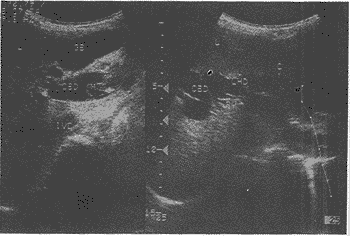

中国超声医学杂志990735 患者女性,11岁。长跑后突感右上腹胀痛、阵发性剧痛伴恶心、呕吐。在外院抗炎对症 治疗效果欠佳,患者逐渐出现食欲减退、全身乏力发热,来我院就诊。超声检查见:肝左叶 见5.9cm×7.3cm液性暗区,界尚清,周边为较厚的低回声带,不规整,突入液性暗区,暗 区内见少许不规则光带回声,并可见一独立完整的小光圈。此回声暗区与肝左管相沟通,继 续扫查可见肝内外胆管重度扩张,呈囊状,胆总管扩张为2.7cm,在其下段内见一光带折叠 缠绕形成一大小约1.43cm×3.92cm不均质团块,此处胆管壁与团块分界清,观察期间团块 无形态大小的改变。胆囊大小为8.6cm×2.7cm(图1)。B超提示:肝包虫内囊破入胆管并胆 总管下段包虫内囊梗阻;2.肝左叶液性病灶:肝包虫破裂后残腔(内含子囊);3.胆囊肿大 、胆囊炎。术前包虫皮内试验阳性。

L:肝脏,GB:胆囊,CBD:胆总管,PV:门静脉,M:团块,CY:液性病灶 ,LHD:左肝管,IVC:下腔静脉,P:胰腺

图1 肝包虫破入胆道